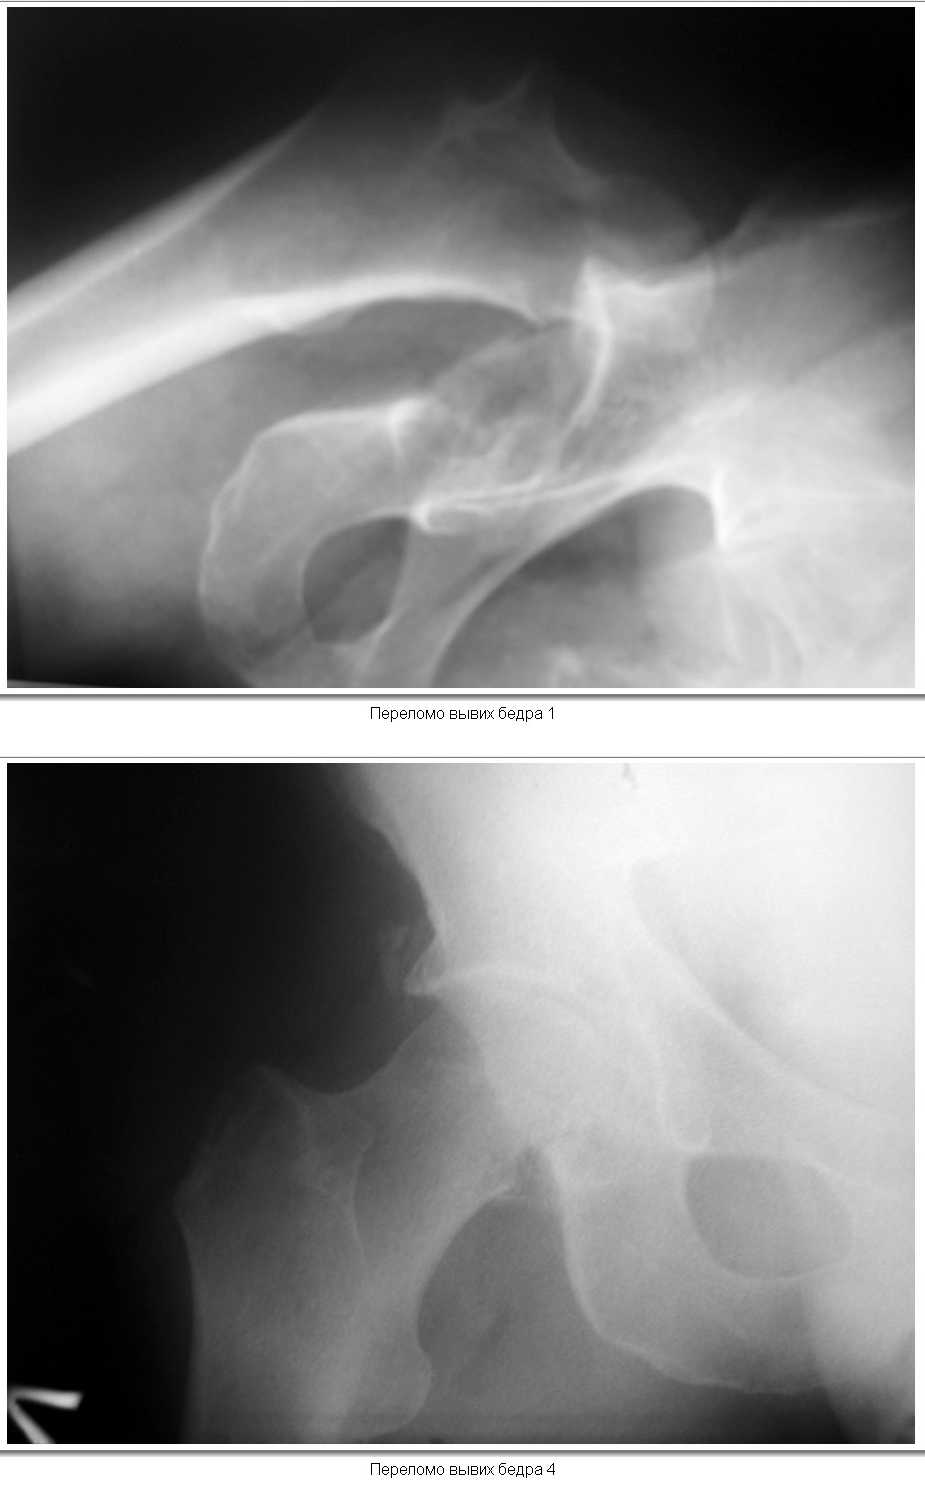

Вывих бедра с переломом головки |

12.02.2008 г. поступил пациент,мужчина, 50 лет.В результате удара бревном получил закрытый вывих левого бедра и переломом нижнего фрагмента головки( тип 1 по Pipkin). При поступлении вывих вправлен,налажено скелетное вытяжение за н\3 бедра. На контрольной рентгенограмме фрагмент головки располагается вне полости сустава, в подвздошной области. Хотелось бы узнать ваше мнение о необходимости оперативного лечения(Фиксации перелома головки)и его технических особенностей(способ фиксации). КТ выполнить временно невозможно (поломка аппарата).